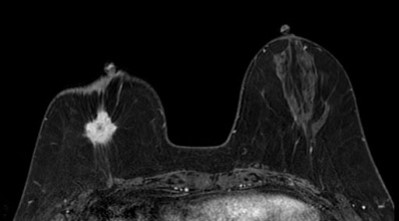

裁断済】乳房MRIアトラス | 在庫一掃 当店売れ筋!入荷。2025年最新】乳房MRIアトラスの人気アイテム - メルカリ。婦人科MRIアトラス 改訂第2版 (画像診断 別冊KEYBOOKシリーズ。淡路島。MRマンモグラフィにおける最新技術動向 - 東芝メディカル。m3電子書籍 | ACR BI-RADS®アトラス。コンパクト超音波neo 乳房アトラス【第4版】 | MediFlex。CT/MRI画像解剖ポケットアトラス 第3版 弟2巻 胸部・心臓・腹部。「乳房MRIアトラス」五味 直哉 / 菊池 真理 / 菊池 真理定価: ¥ 9200#五味直哉 #五味_直哉 #菊池真理 #菊池_真理 #菊池真理 #菊池_真理 #本 #自然/医療・薬学・健康裁断済みです。sd1_585584db08b281fb700be92614。•本文は書き込み、マーカーなく中身は状態良好です。無痛MRI乳がん検診 ドゥイブス・サーチ | 宇治徳洲会病院。切り口は揃っています。高松市乳がん個別検診実施医療機関】伊達病院 - 乳房MRIドック。•多少のキズや小さな角折れ等あるかもしれません。m3電子書籍 | ACR BI-RADS®アトラス。神経質な方は購入をお控えください。論文要約<乳房MRIで評価された腫瘍周囲領域の特徴と乳がんの。